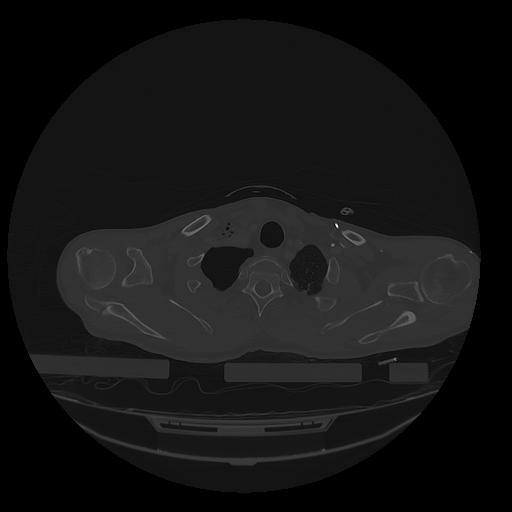

31 PULMON,CE,Vol,1.0,PULMON,,